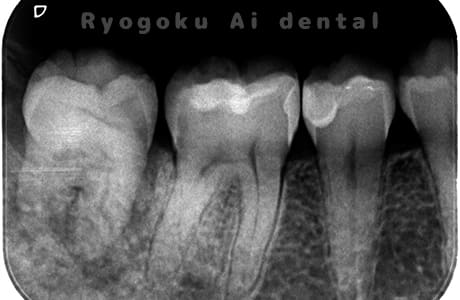

Case01

-

- 原因

- 慢性根尖性歯周炎

- 治療期間

- 3ヶ月

- 治療内容

- 自家歯牙移植手術+マイクロエンド+ダイレクトボンディング

- 治療費用

- ¥220,000

他院で根尖病変が大きく、抜歯と判断され、インプラント手術を提案された患者様です。親知らずが残存していたため、自家歯牙移植手術を行いました。

<リスク・副作用>

治療後、痛みや違和感、出血、腫れなどが出る事があります。喫煙者、糖尿病などの方の場合、歯が生着しない場合があります。